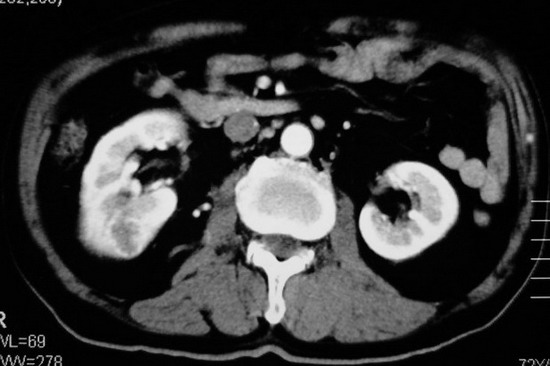

以下是引用杀毒软件在2008-11-17 19:15:00的发言:[br]考虑------右肾癌合并肾静脉---同侧肾上腺受侵可能性大

以下是引用zjzjr在2008-11-17 20:45:00的发言:[br]考虑------右肾癌合并肾静脉---同侧肾上腺受侵可能性大及腹膜后淋巴结转移.